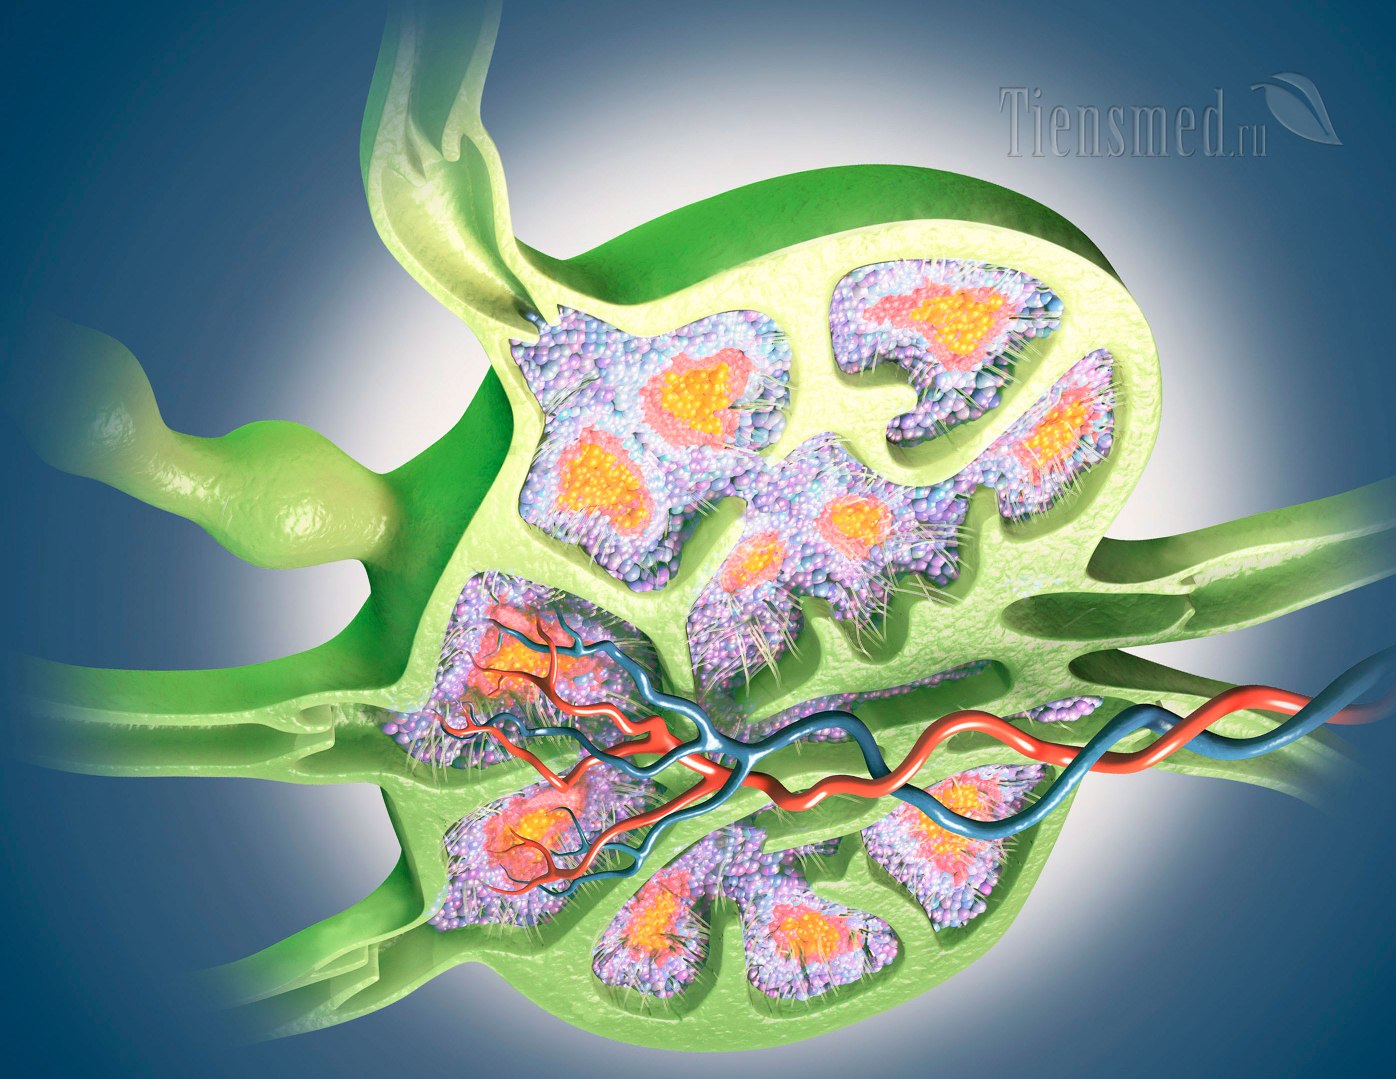

Изображения и схемы: как выглядит лимфа